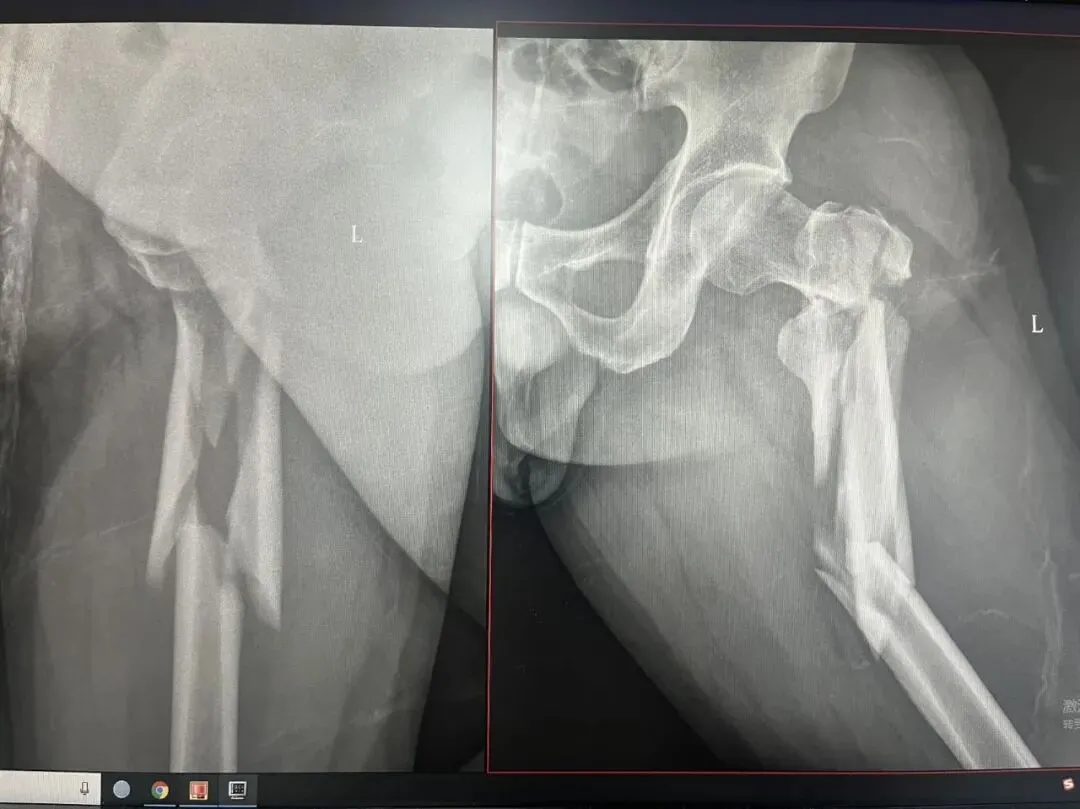

先看片子

中老年男性,高处坠落伤,如此长节段股骨近端骨折比较少见。手术治疗是必须的,患者等待期间血栓风险极高。而且患者卧床骨牵引期间护理极其不方便,给家人造成很大困惑为早点解决患者病痛,入院后积极抗凝预防血栓,伤后第3天手术治疗。我们选择PFNA闭合复位内固定。手术还算顺利。